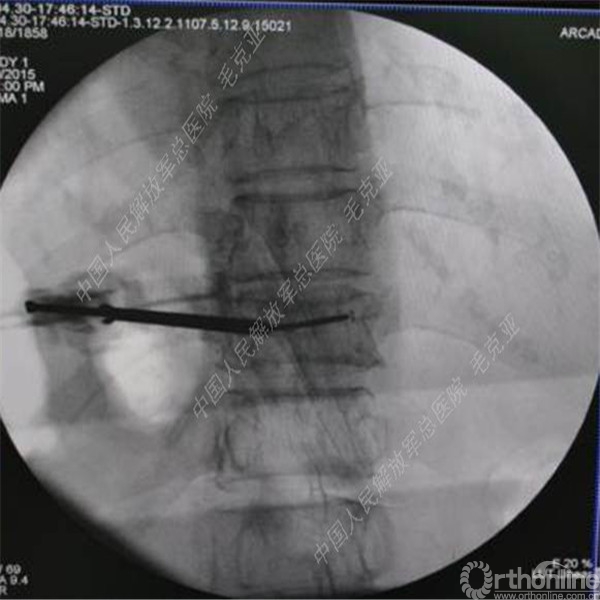

导语:随着社会老龄化的不断加速,骨质疏松性椎体压缩骨折作为一种普遍存在的老年骨科疾病已经成为现今骨科界的一个热点话题。传统的保守疗法治疗效果不佳,而现有的椎体增强技术又具有多种风险和缺陷。针对这种现状,中国人民解放军总医院毛克亚教授提供了一种新的解决方法。